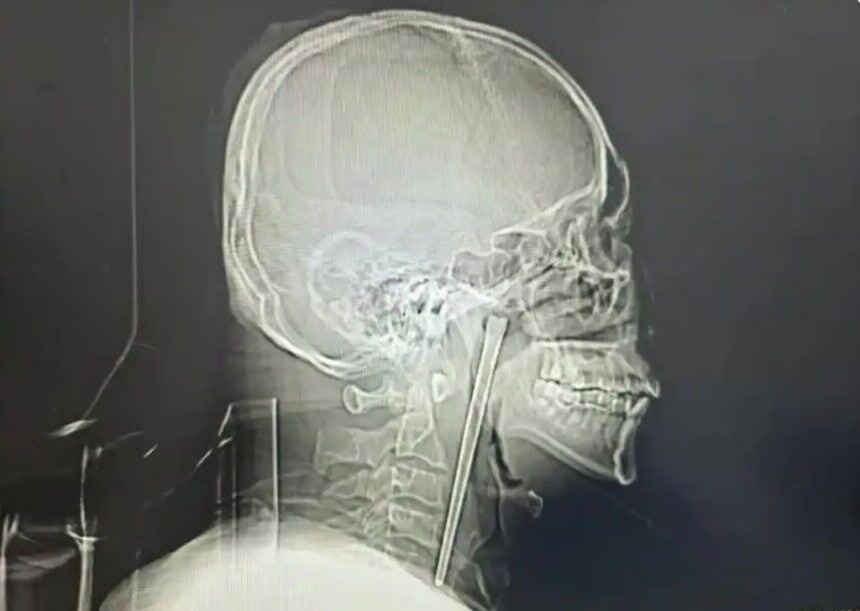

• 조선일보목에 12㎝ 젓가락 박힌 채 8년... 中 남성, 뒤늦게 제거 수술한 사연